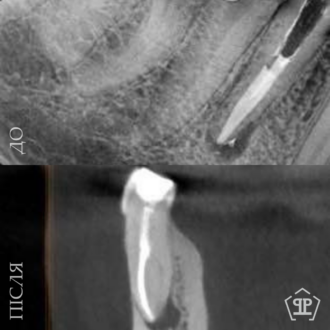

Роботи лікаря Все работы ⋅⋅⋅